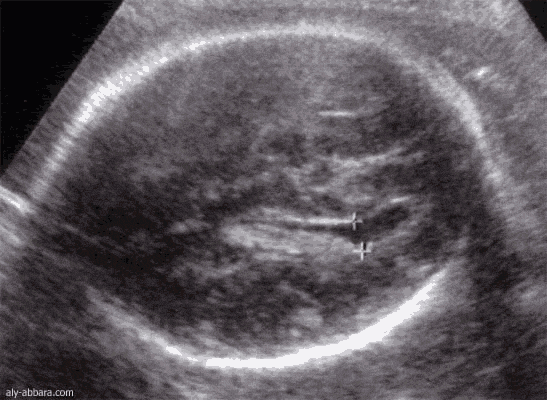

Cerveau fœtal : Carrefour ventriculaire postérieur

(28 semaines d'aménorrhée)